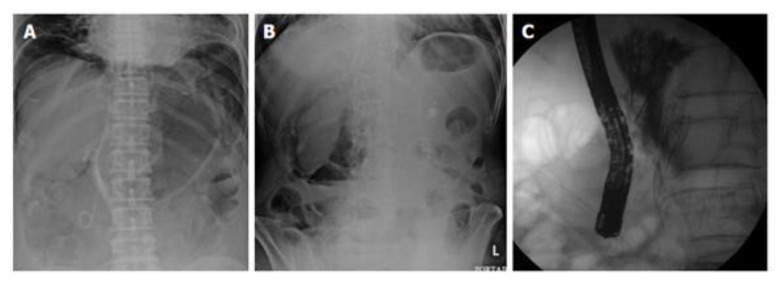

内镜逆行胰胆管造影(ERCP)已成为治疗胆道和胰腺疾病的基本治疗方式。然而,穿孔仍然是ERCP和内镜下括约肌切开术最令人担忧的并发症之一。ERCP术后穿孔的发生率相对较低,但相关死亡率可达7.8%。穿孔的诊断和处理取决于损伤的机制、位置和程度,正如临床和放射学所显示的那样。本文详细介绍了ercp相关穿孔的原因、分类、诊断、管理和预防策略。

Endoscopic retrograde cholangiopancreatography (ERCP) has become an essential treatment modality for managing biliary and pancreatic disorders. However, perforation remains one of the most concerning complications associated with ERCP and endoscopic sphincterotomy. While the incidence of perforation following ERCP is relatively low, the associated mortality rate can reach 7.8%. Diagnosis and management of perforations depend on the injury's mechanism, location, and extent, as clinical and radiographic findings suggest. This paper provides a detailed overview of the causes, classification, diagnosis, management, and prevention strategies for ERCP-related perforations.